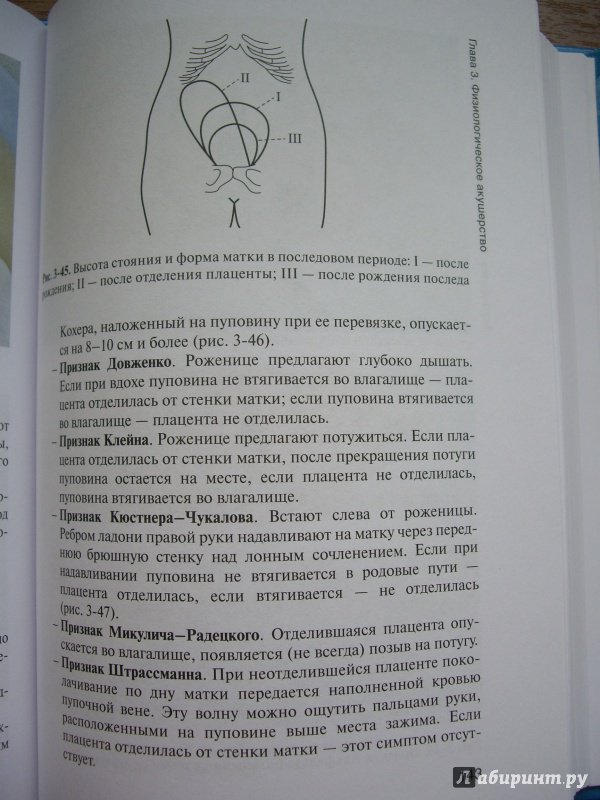

Медицинская визуализация: Признак Кюстнера-Чукалова